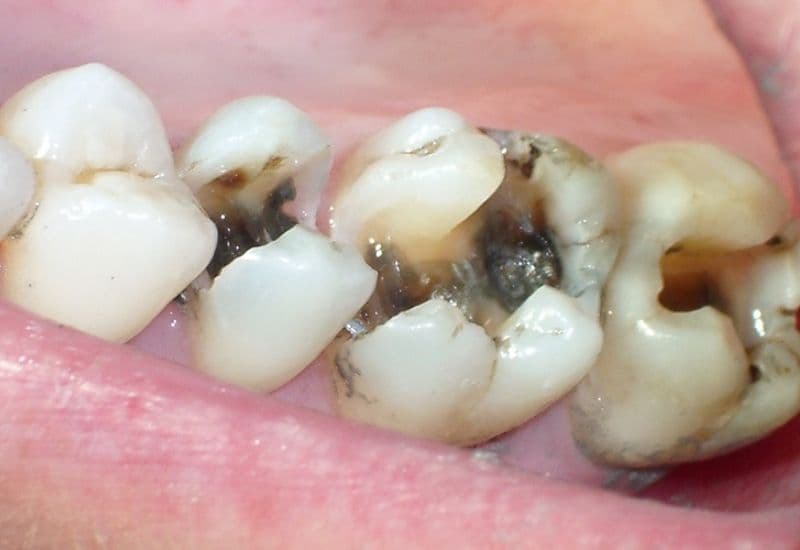

Răng sâu là tình trạng men răng và ngà răng bị phá hủy do vi khuẩn tấn công. Quá trình này bắt đầu khi vi khuẩn trong miệng kết hợp với thức ăn thừa tạo thành mảng bám răng. Các vi khuẩn này tiết ra axit làm hòa tan khoáng chất trên bề mặt răng, tạo thành các lỗ sâu nhỏ ban đầu.

Nhiều người thường chủ quan với răng sâu giai đoạn đầu vì nghĩ rằng đó chỉ là vấn đề nhỏ. Nhưng thực tế, răng sâu nếu không được điều trị kịp thời sẽ tiến triển thành những biến chứng nghiêm trọng, thậm chí đe dọa tính mạng.

Răng sâu nếu không điều trị kịp thời có thể gây biến chứng nguy hiểm.